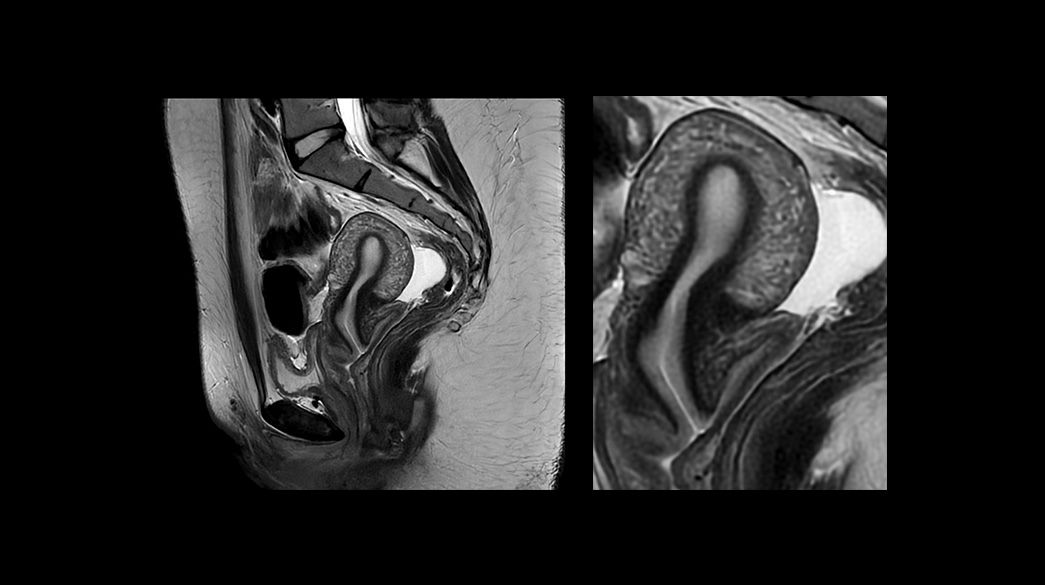

PROView-DL1040-x-585

Read case study ico-caret-right